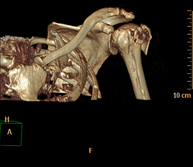

- TC Hombro

Exploración radiológica que mediante un sistema de rayos X y detectores que giran alrededor del paciente, reconstruyendo las imágenes por ordenador (TC Multidetector), permite el estudio de huesos, músculos y articulaciones del hombro. - TC Codo